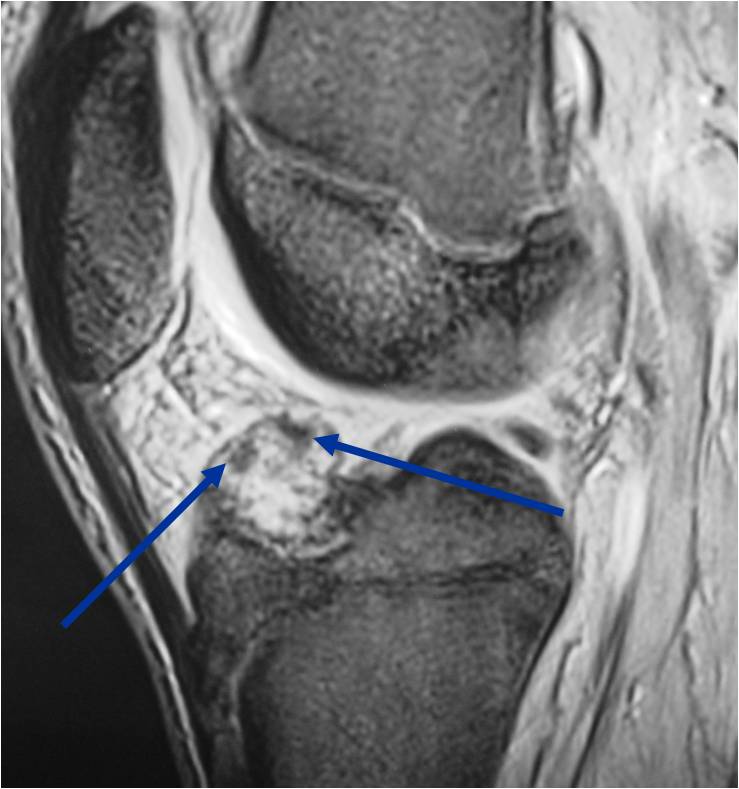

- (MRI appearance)

- Geographic, well circumscribed lesion in the epiphysis

- Intermediate Signal on T1

- High signal on T2 mixed with low signal areas (low signal areas proposed to be secondary to lysosomal content of highly cellular areas)

- Fluid/Fluid levels demonstrated in tumors that have undergone ABC change (aneurysmal bone cyst change)

- Extensive Surrounding edema is common

- Joint effusion in 30-50% of cases